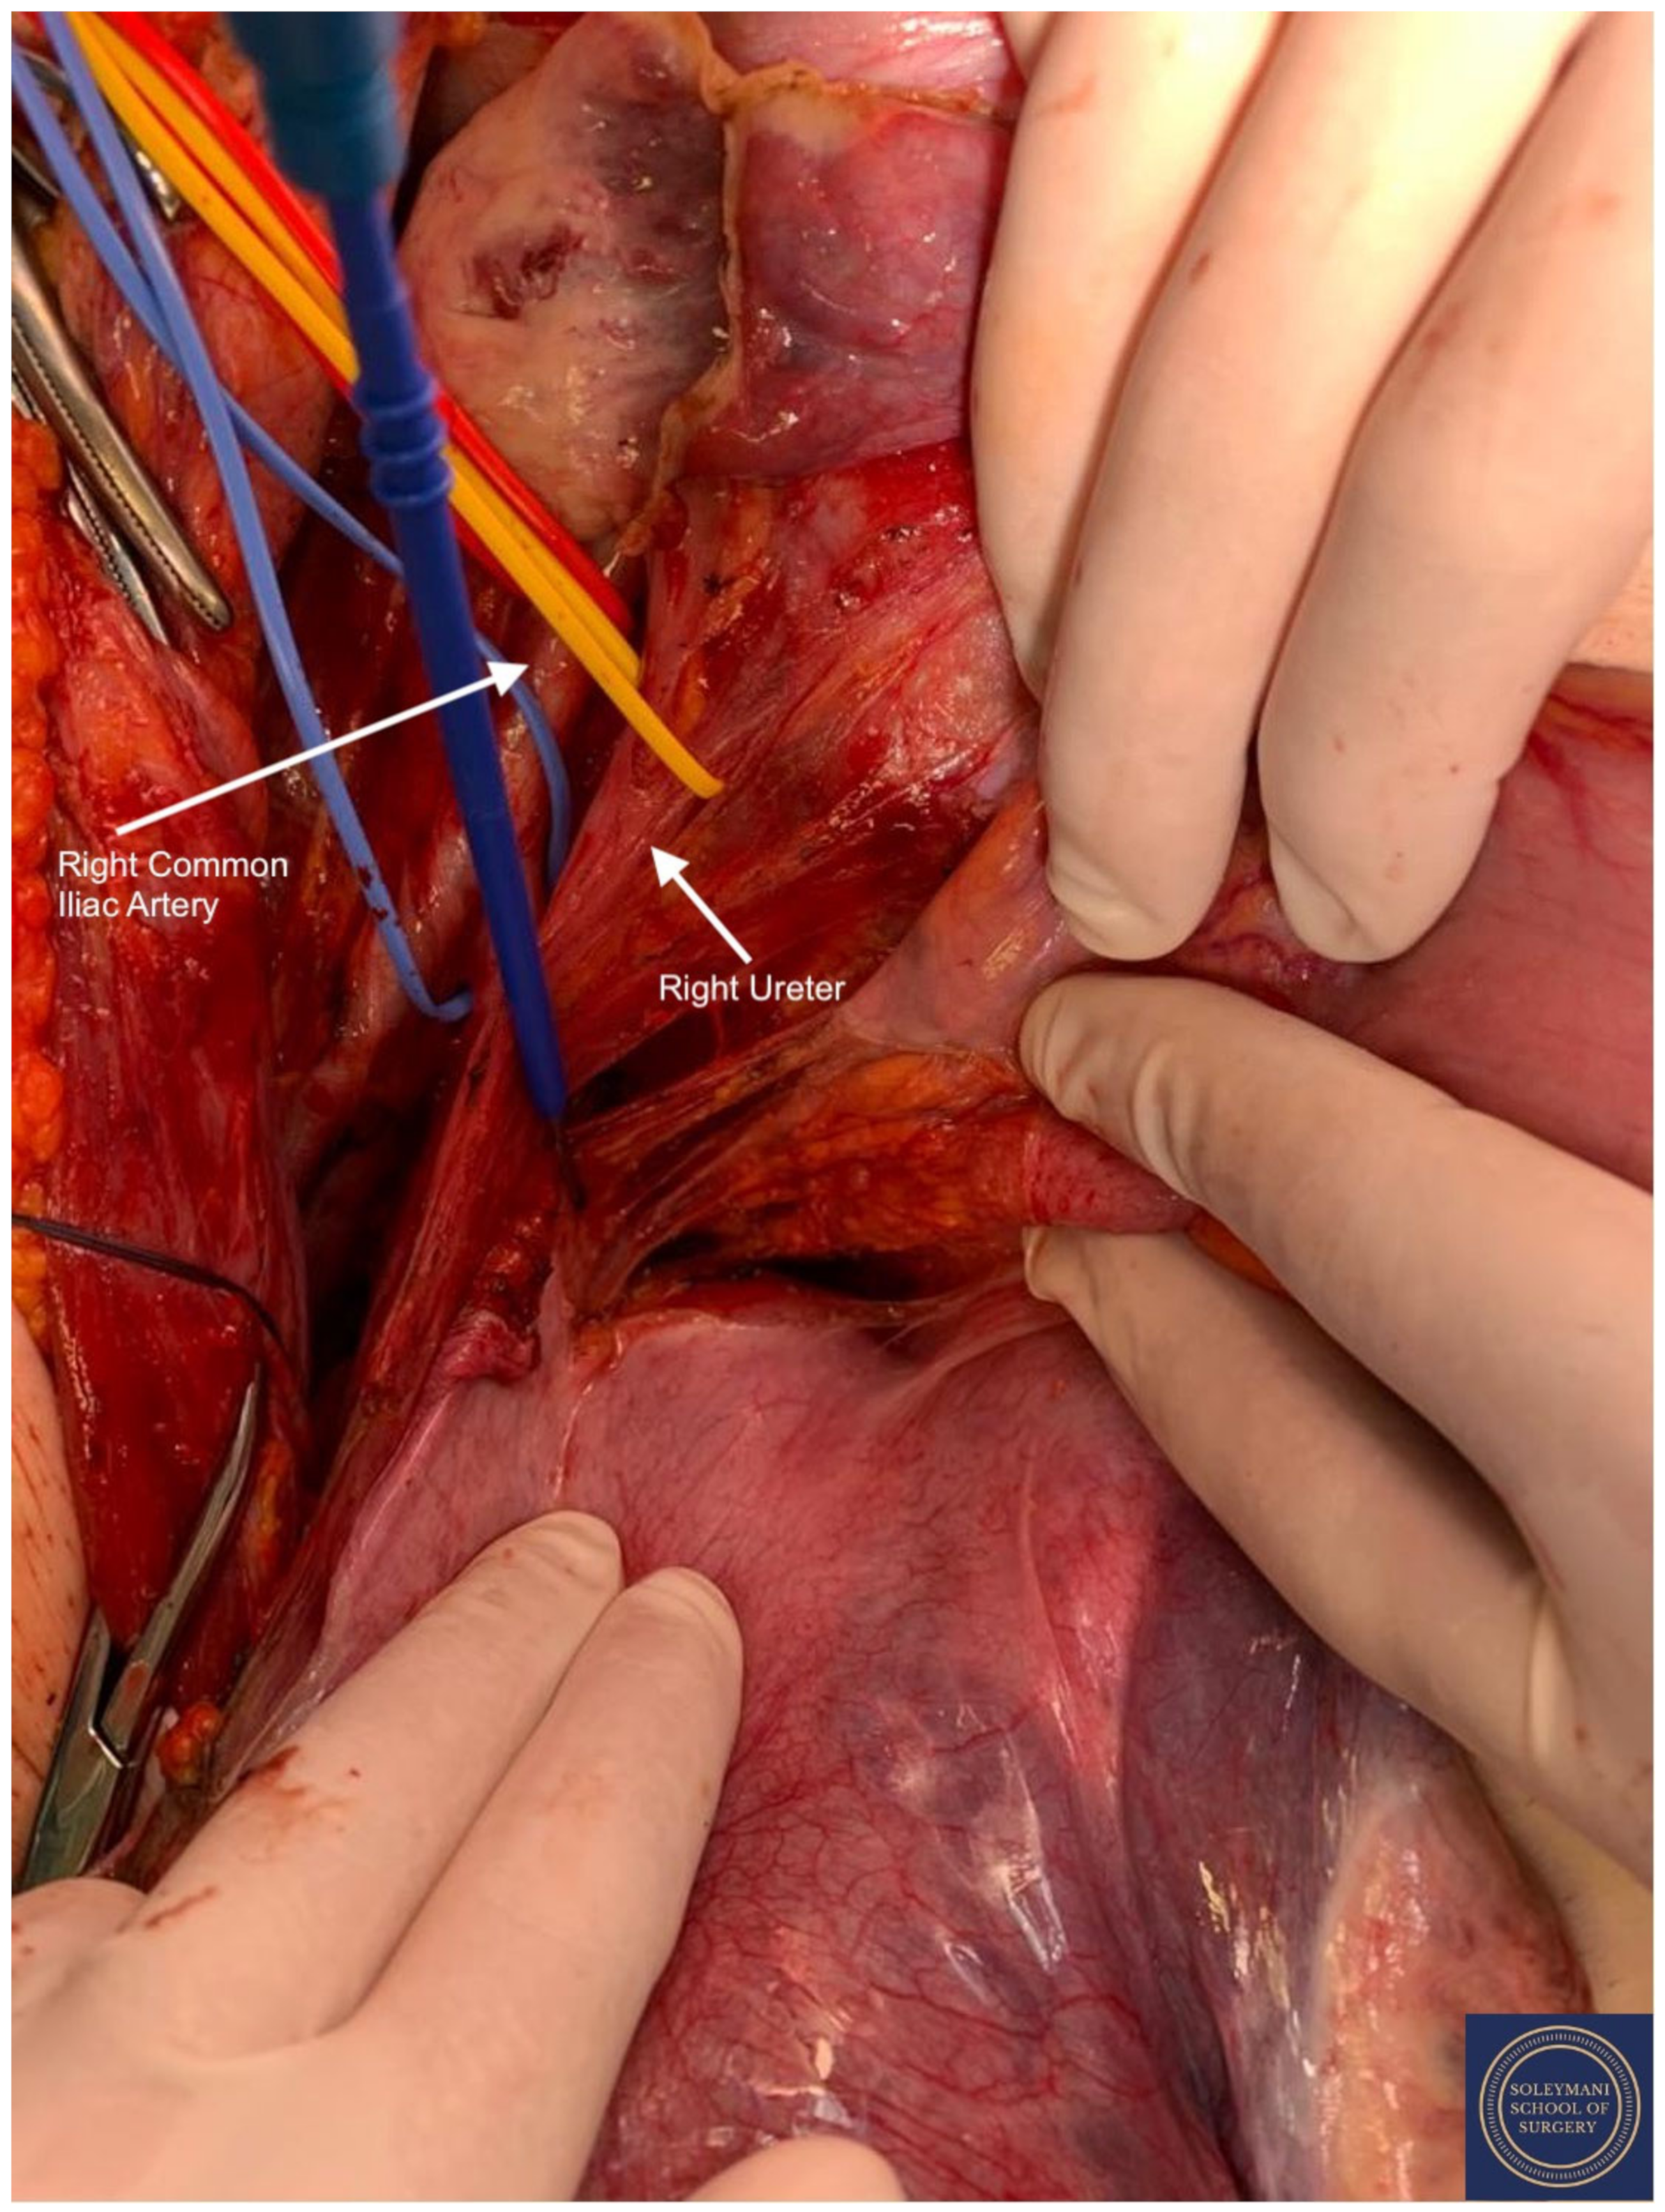

- Exposure of the infundibulo-pelvic ligaments and ureters were achieved with mobilization of the cecum, duodenum, and descending and sigmoid colon to the level of the common iliac vessel bifurcation with identification of the superior hypogastric plexus. The ureters, common iliac and internal and external iliac vasculatures were slung.